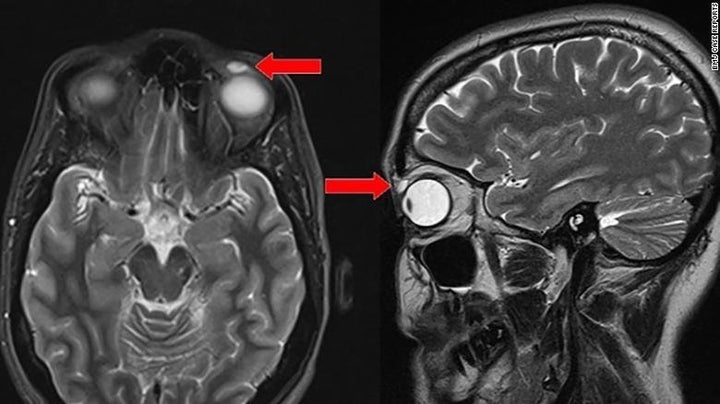

Woman Gets Contact Lens Stuck In Eye For 28 Years

Case in point: A 42-year-old woman in Great Britain who lost a lens when she was a teen, only to have doctors discover it embedded in her eye 28 years later.

According to the medical journal BMJ Case Reports, the patient went to the doctor after she discovered a pea-sized lump below her left eyebrow.

The cyst was visible on an MRI and cause the woman’s left eyelid to droop, according to CNN.

When doctors went in to remove the cyst, they discovered a rigid contact lens that somehow migrated into the eyelid, according to USA Today.

At first, the woman couldn’t recall how the contact lens got stuck in her peepers. Then her mom remembered the patient losing a lens during a badminton game when the patient was just 14.

Since the woman had no symptoms, she figured the lens had simply fallen out and gone missing.

“The patient never wore [rigid gas-permeable] lenses following this incident. We can infer that the RGP lens migrated into the patient’s left upper eyelid at the time of trauma and had been in situ for the last 28 years,” the authors said in their report.

Once the cyst and the lens were removed from the woman’s eyes, her peepers went back to normal.